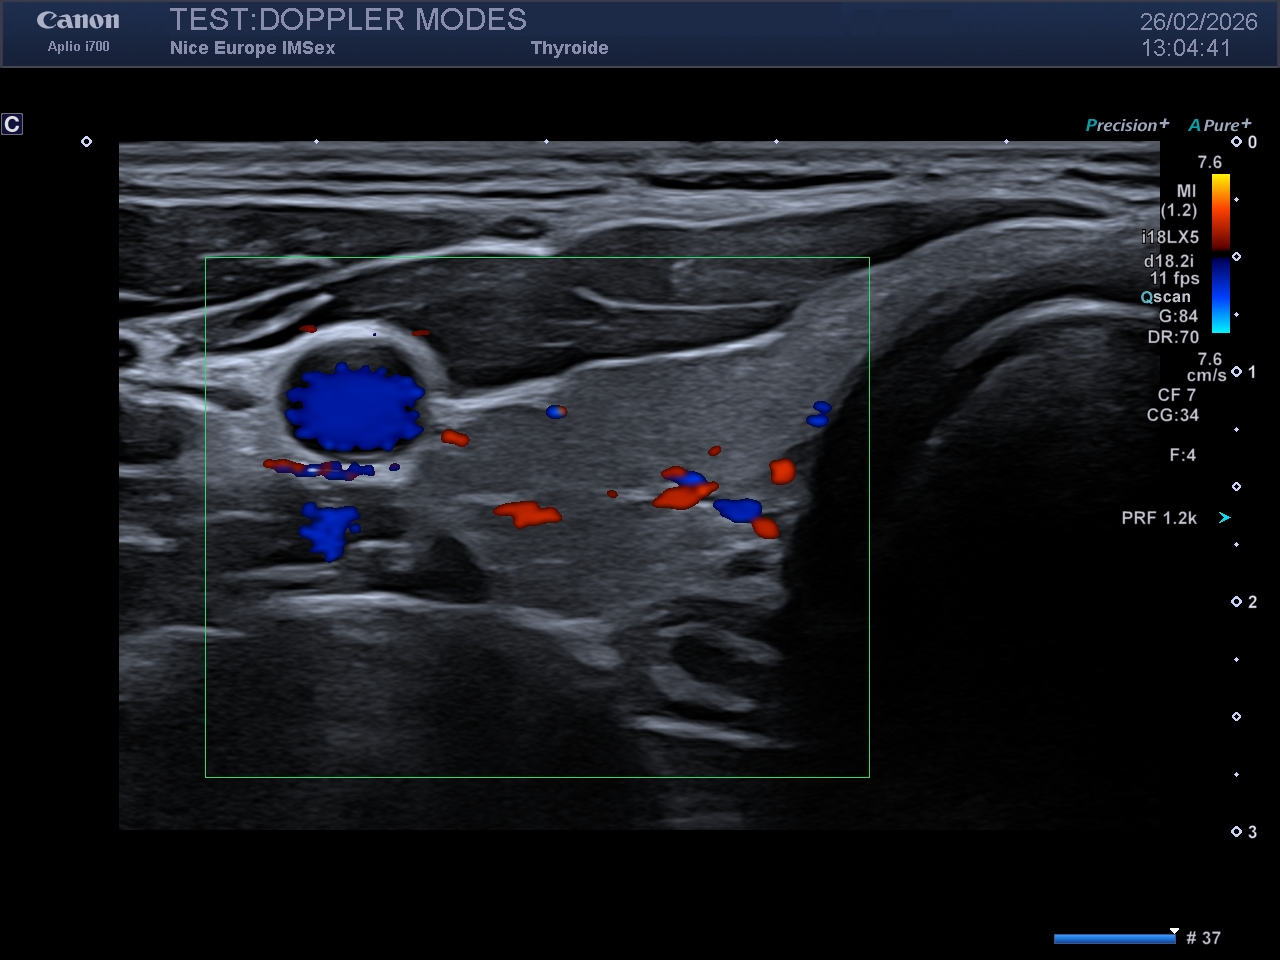

Le Doppler couleur est conçu pour cartographier la vitesse moyenne et la direction du flux sanguin. Il traduit ces informations en une carte de couleur qui se superposera à l'image échographique "mode B" (en nuances de gris).

Sur un réglage dit "usine", ou par défaut :

- le flux rouge se rapproche de la sonde

- le flux bleu s'éloigne de la sonde

Légende : Image en Doppler couleur d'un rein droit

Ces informations quantitatives sont codées chromatiquement et superposées à l'imagerie morphologique en mode B. Par défaut (réglages d'usine), la convention chromatique est généralement la suivante :

Rouge : Flux se dirigeant vers la sonde (décalage de fréquence positif).

Bleu : Flux s'éloignant de la sonde (décalage de fréquence négatif).

Une règle d'or d'interprétation : Il est impératif de souligner que cette colorisation est purement arbitraire et modifiable à tout instant par l'opérateur (inversion de la carte couleur). Par conséquent, la vérification systématique de l'échelle couleur (la barre colorimétrique affichée en marge de l'écran) doit être un réflexe absolu et incontournable avant toute conclusion hémodynamique directionnelle.